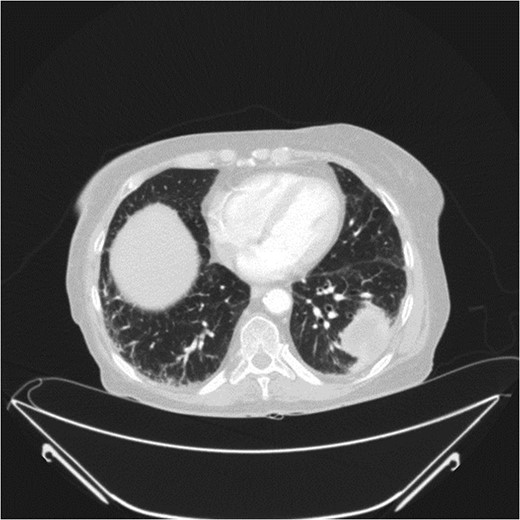

A 78-year-old female presented with worsening abdominal pain over 1 week, with onset of symptoms occurring 3 months prior. No history of recurrent fever or weight loss was elicited. There were no changes in bowel habits and she denied melena or hematochezia. She endorsed a normal colonoscopy three years prior. Of note, she was diagnosed with a biopsy proven squamous cell cancer of her left lower lobe 4 months earlier (Fig. 1). A PET scan performed just three weeks prior to her presentation demonstrated significant FDG uptake in the left lower lobe as well as the cecum, with no convincing evidence of regional nodal disease in the lungs (Figs 2 and 3).

At presentation her vital signs were stable. Abdominal exam revealed exquisite tenderness in the right lower quadrant, with no evidence of digital clubbing. Blood-work revealed an elevated WBC of 15.6. A CT scan demonstrated a 4.3 cm annular mass within the cecum, suspicious for a primary colonic malignancy, as well as an 8.6 × 8.2 cm2 lobulated gas-containing abscess with extension in to the lateral abdominal wall (Figs 4 and 5).